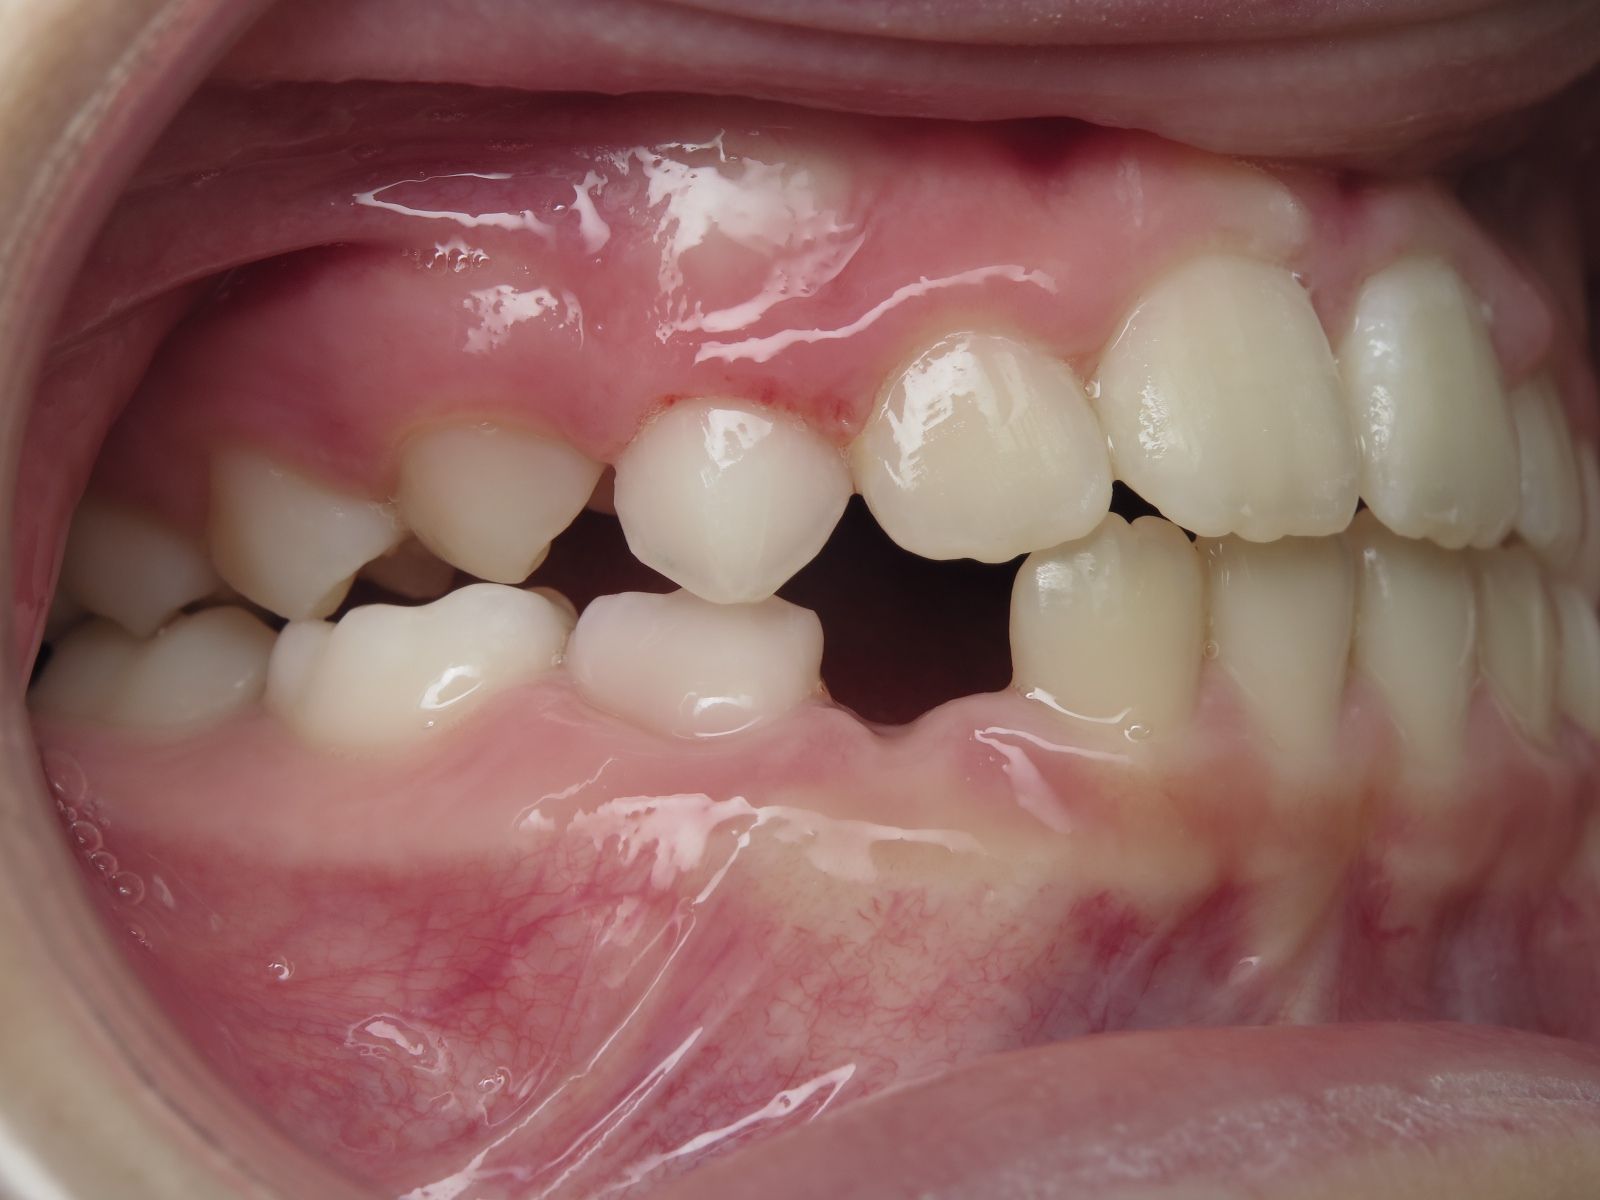

appareillage mobile pendant 22 mois